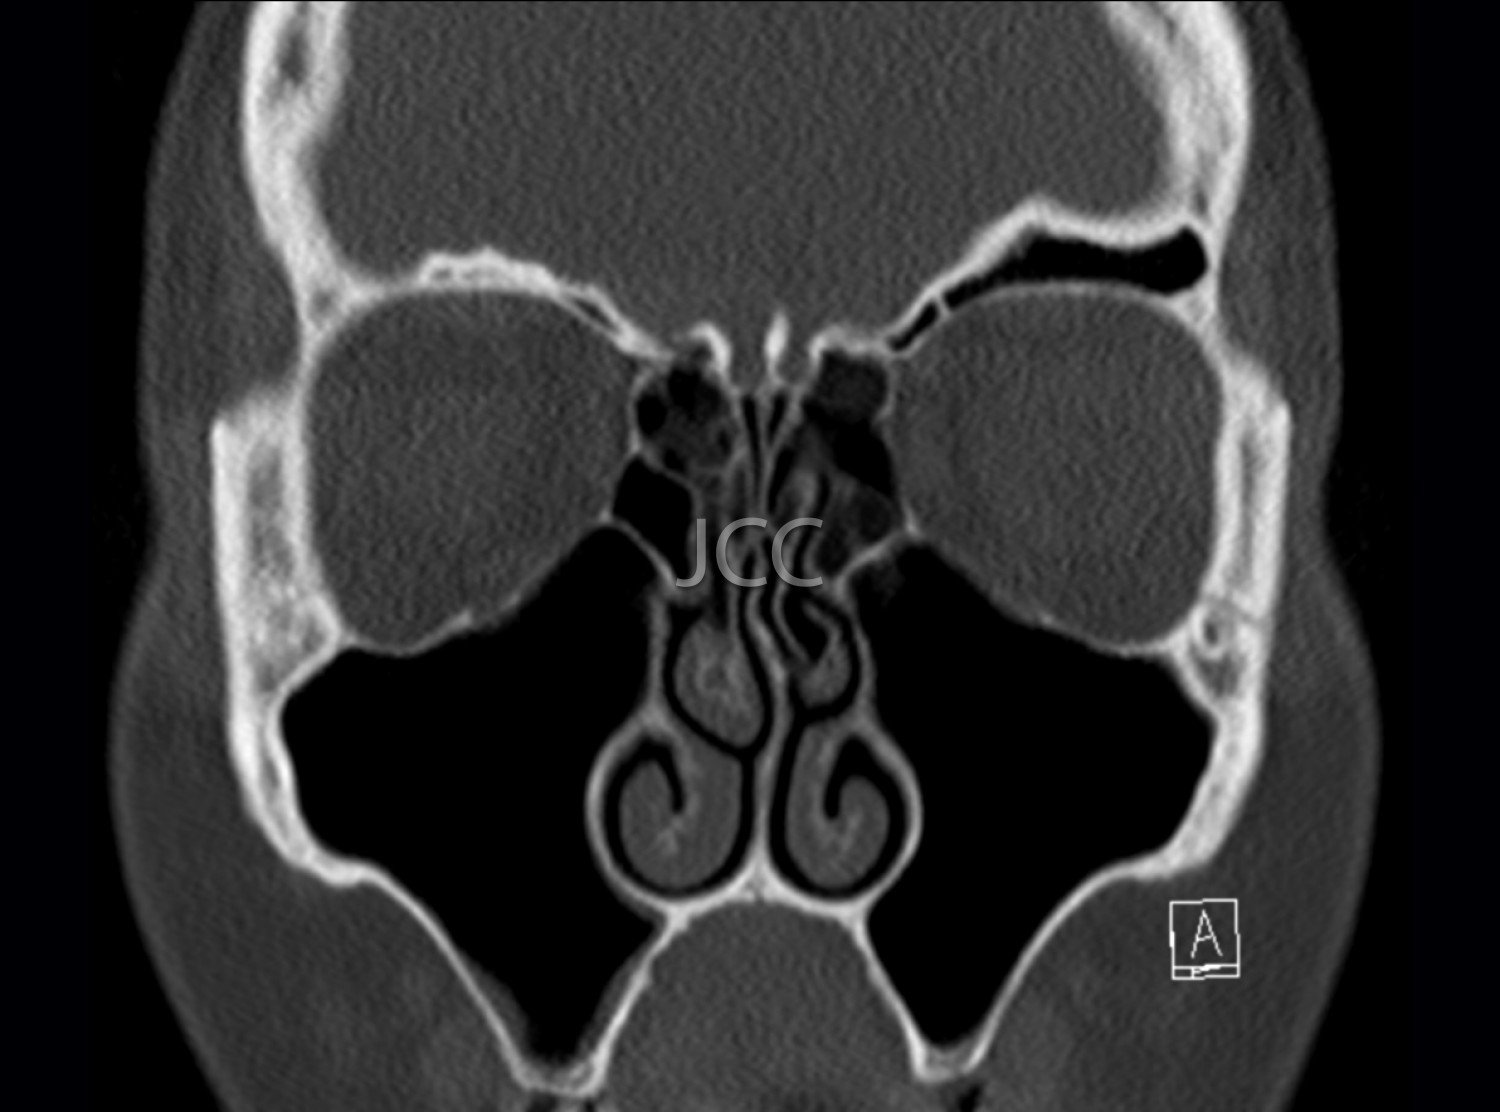

Tomografia Axial Computorizada - TAC Seios Perinasais

A Tomografia Axial Computorizada (TAC) - Dupla Energia - 256 cortes é uma técnica de diagnóstico que permite a avaliação de várias partes do corpo humano, incluindo pulmões, fígado, pâncreas, rins, coração, estruturas vasculares e estruturas ósseas.